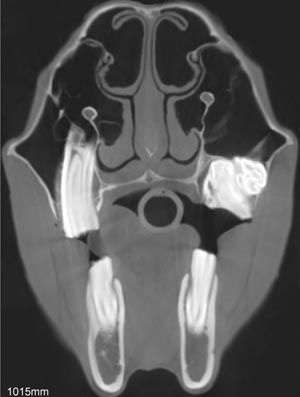

Palatoschisis is the technical term for cleft palate [schist- = split as in schistosomus reflexus]. Cleft palates can be unilateral or bilateral. The bilateral type is symmetrical and the ventral edge of the nasal septum is easily seen. In the unilateral type the ventral edge of the nasal septum is fused to the normal side hard palate so that it is hard to see.

Bilateral cleft palate is more common than unilateral and unilateral is usually associated with incomplete clefts and cleft lip (hare lip because it resembles the upper lip of a hare). In animals cleft palate is far more common than cleft lip (cheiloschisis). The University of Minnesota museum collection has 19 cleft palate specimens but only 3 of them have a cleft lip. Cleft palate may occur associated with other defects such as dicephalus or achondroplasia or it may not be associated with other defects. In our collection 8 of 19 cleft palates were associated with other defects.

The Kentucky study of equine congenital defects found 24 cases of cleft palate in 608 foals with defects (AJVR 46:353-358, 1985). In contrast, a multispecies study of congenital defects found only 40 cleft palates among 6,455 animals with congenital defects (AJVR 31:1871-1879, 1970).